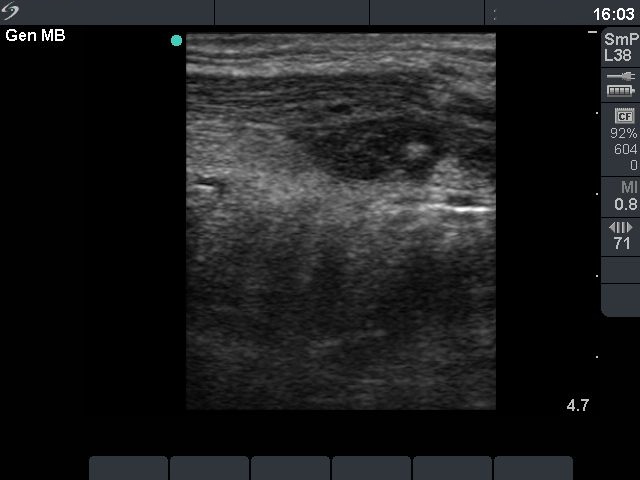

Before sclerotherapy (first row):

Clinical presentation: a 48-year-old man with repeatedly aspirated and recurred thyroid cyst causing complaints.

Palpation: there was a large nodule in the isthmic part of the thyroid.

Ultrasound. The size of the lesion was 38x28x39 mm (width x depth x length).FNAC resulted in a benign lesion.